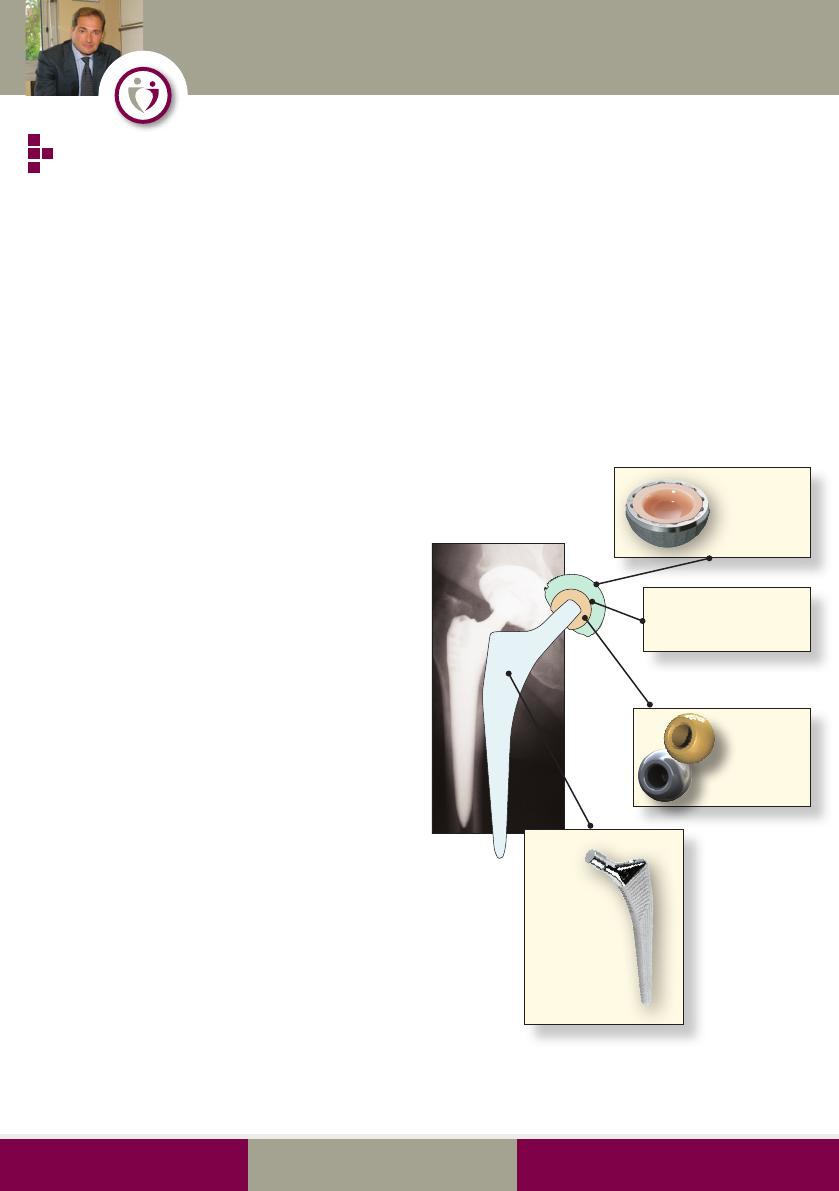

La prothèse de hanche

Le panel des prothèses de hanche est pléthorique

et répond à des philosophies différentes car il faut

de toutes façons faire des compromis (mobilité,

stabilité, risque d’usure de la prothèse). A noter

qu’il faut aussi prendre en compte les choix et les

habitudes du chirurgien.